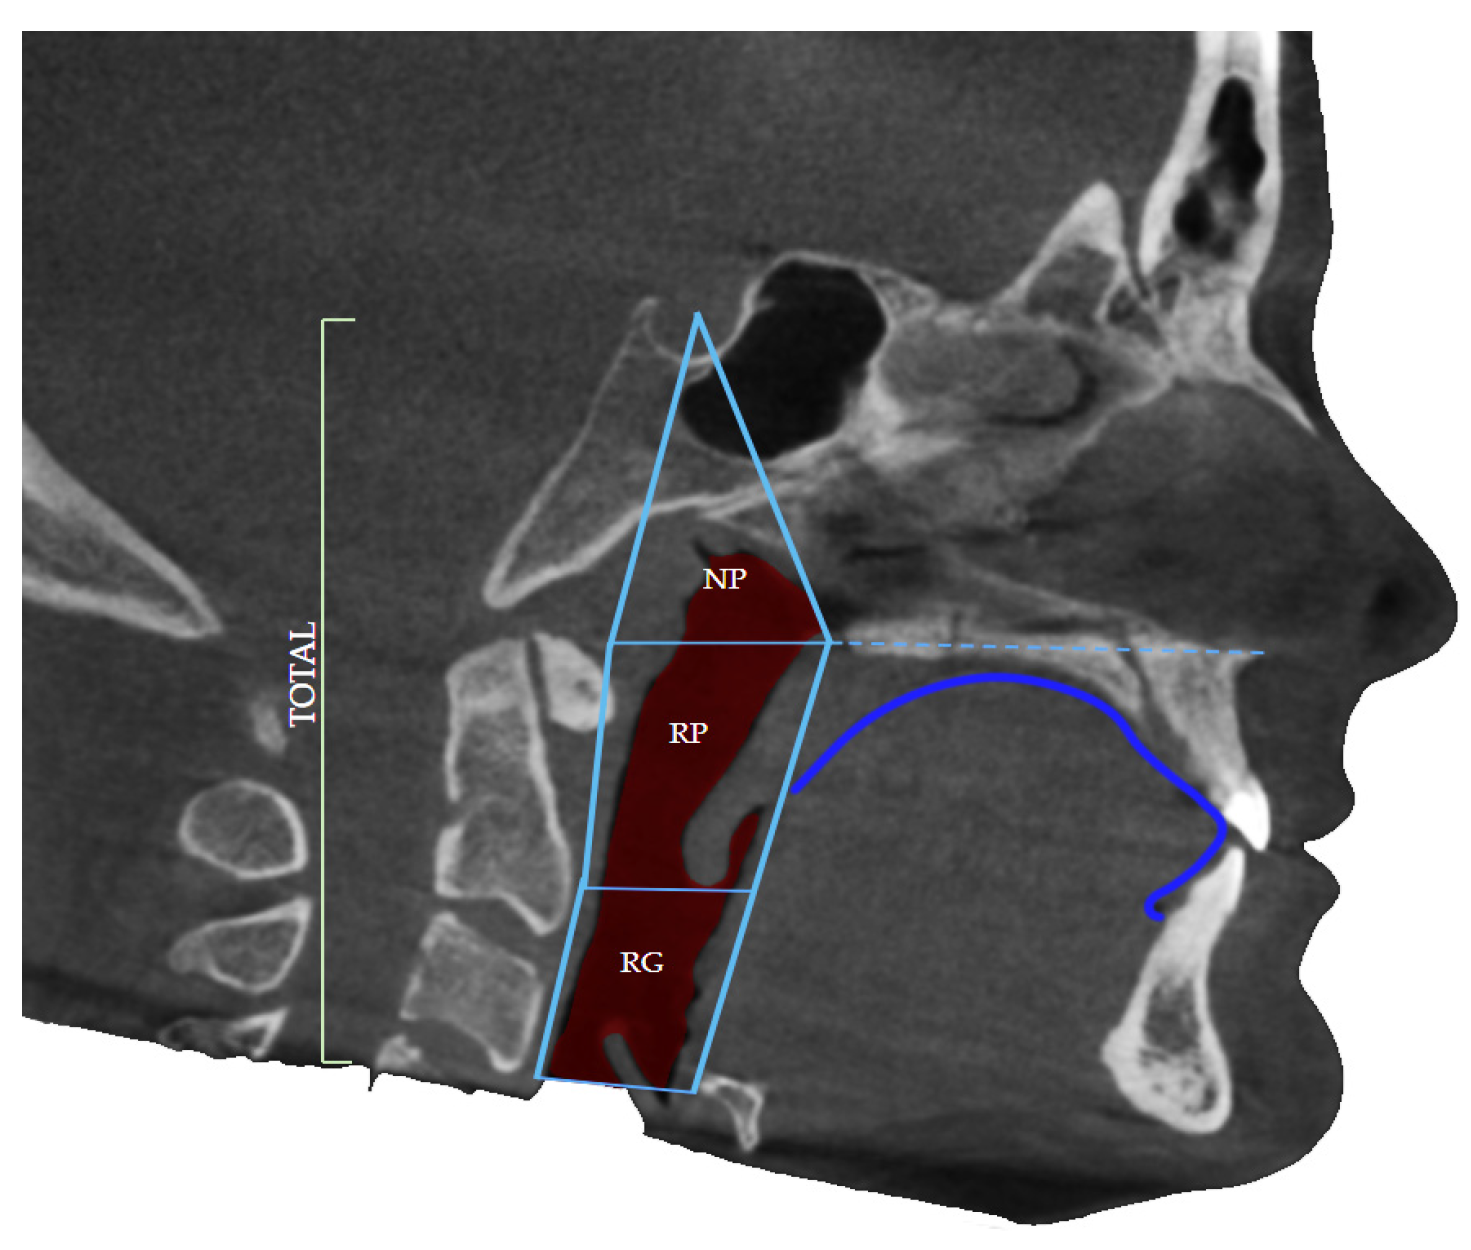

The upper border of the airway was defined by the diagonal line connecting the anatomical point of Sella Turcica and the posterior nasal spine (PNS). Sella turcica of pituitary (hypophyseal) fossa is a midline, dense structure in the sphenoid bone, which houses the pituitary gland. The posterior nasal spine represents the most posterior point of the maxillary line and nasal floor seen on the lateral projection of the CBCT of the patient (Figure 2).

The lower border was defined as the base of the epiglottis, the soft tissue that leads air further into the lungs, dividing the upper respiratory system from the lower, as well as the respiratory system from the digestive system. The borders were defined by the study by dos Santos et al. in 2020 during their trial to correlate airway volume and maximum constriction area location in different dentofacial deformities [1].

Figure 2. Defined borders of the airway volume consist of the nasopharyngeal (NP) portion as well as oropharyngeal regions: retropalatal (RP) and retroglossal (RG) and dorsum linguae identification.